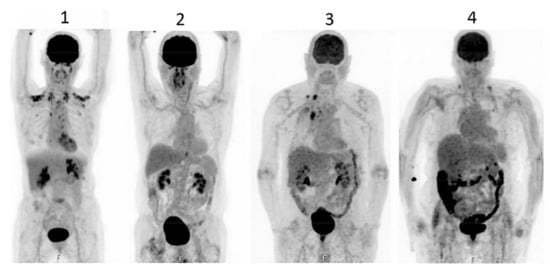

Figure 3.

PET scan was performed in diabetics at different times after interruption of metformin therapy. In patient 4, interruption time was shorter than 48 h and showed strong accumulation of the tracer in the colon. From Schreuder N et al. [173].